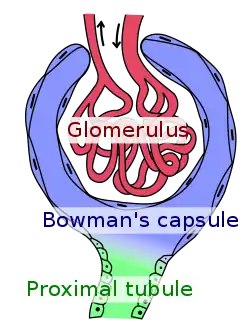

FSGS is primarily a disease of the renal glomerulus, the site of filtration of ions and solutes.[14][15] Podocytes are specialized cells lining the Bowman's capsule that contribute to the filtration barrier, preventing molecules larger than 5 nm from being filtered.[16] FSGS involves damage to the renal podocytes such that larger molecules, most notably proteins, are filtered and lost through the kidney.[17][18] Thus, many of the signs and symptoms of FSGS are related to protein loss.[19]